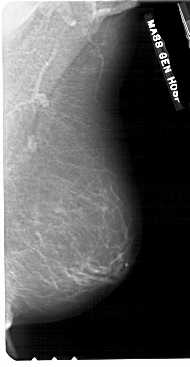

A_1884_1.RIGHT_MLO

RIGHT_MLO LINES 5491 PIXELS_PER_LINE 2836 BITS_PER_PIXEL 12 RESOLUTION 43.5 NON_OVERLAY